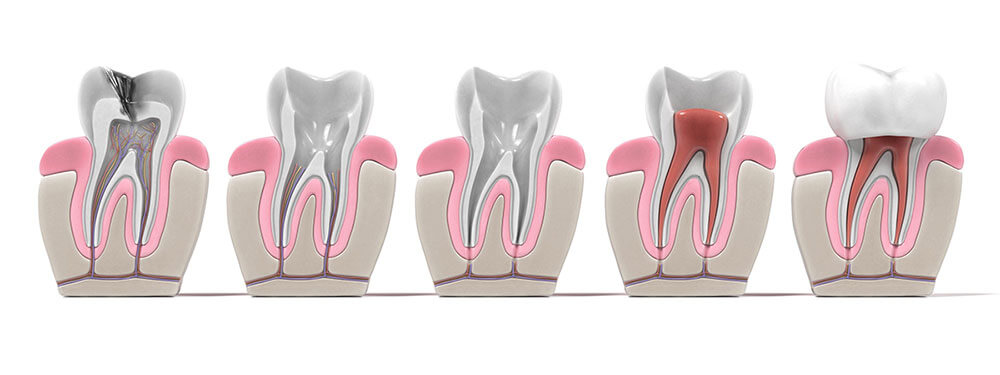

The inside of each tooth is filled with soft tissue known as pulp, which is made up of blood vessels and nerves and serves to keep the tooth alive. Cavities, injuries or trauma, cracks or repeated dental work can compromise the tooth’s outer layers and leave the pulp vulnerable to infection. Root canal therapy involves clearing away the infected or damaged tissue, bacteria and any decay, cleansing the chamber and root canal, filling the space and then sealing the tooth to prevent any further damage. Typically, we’ll place a crown over the tooth to protect it and restore your smile. In the vast majority of cases, with good oral hygiene and regular dental visits, treatment will last a lifetime.